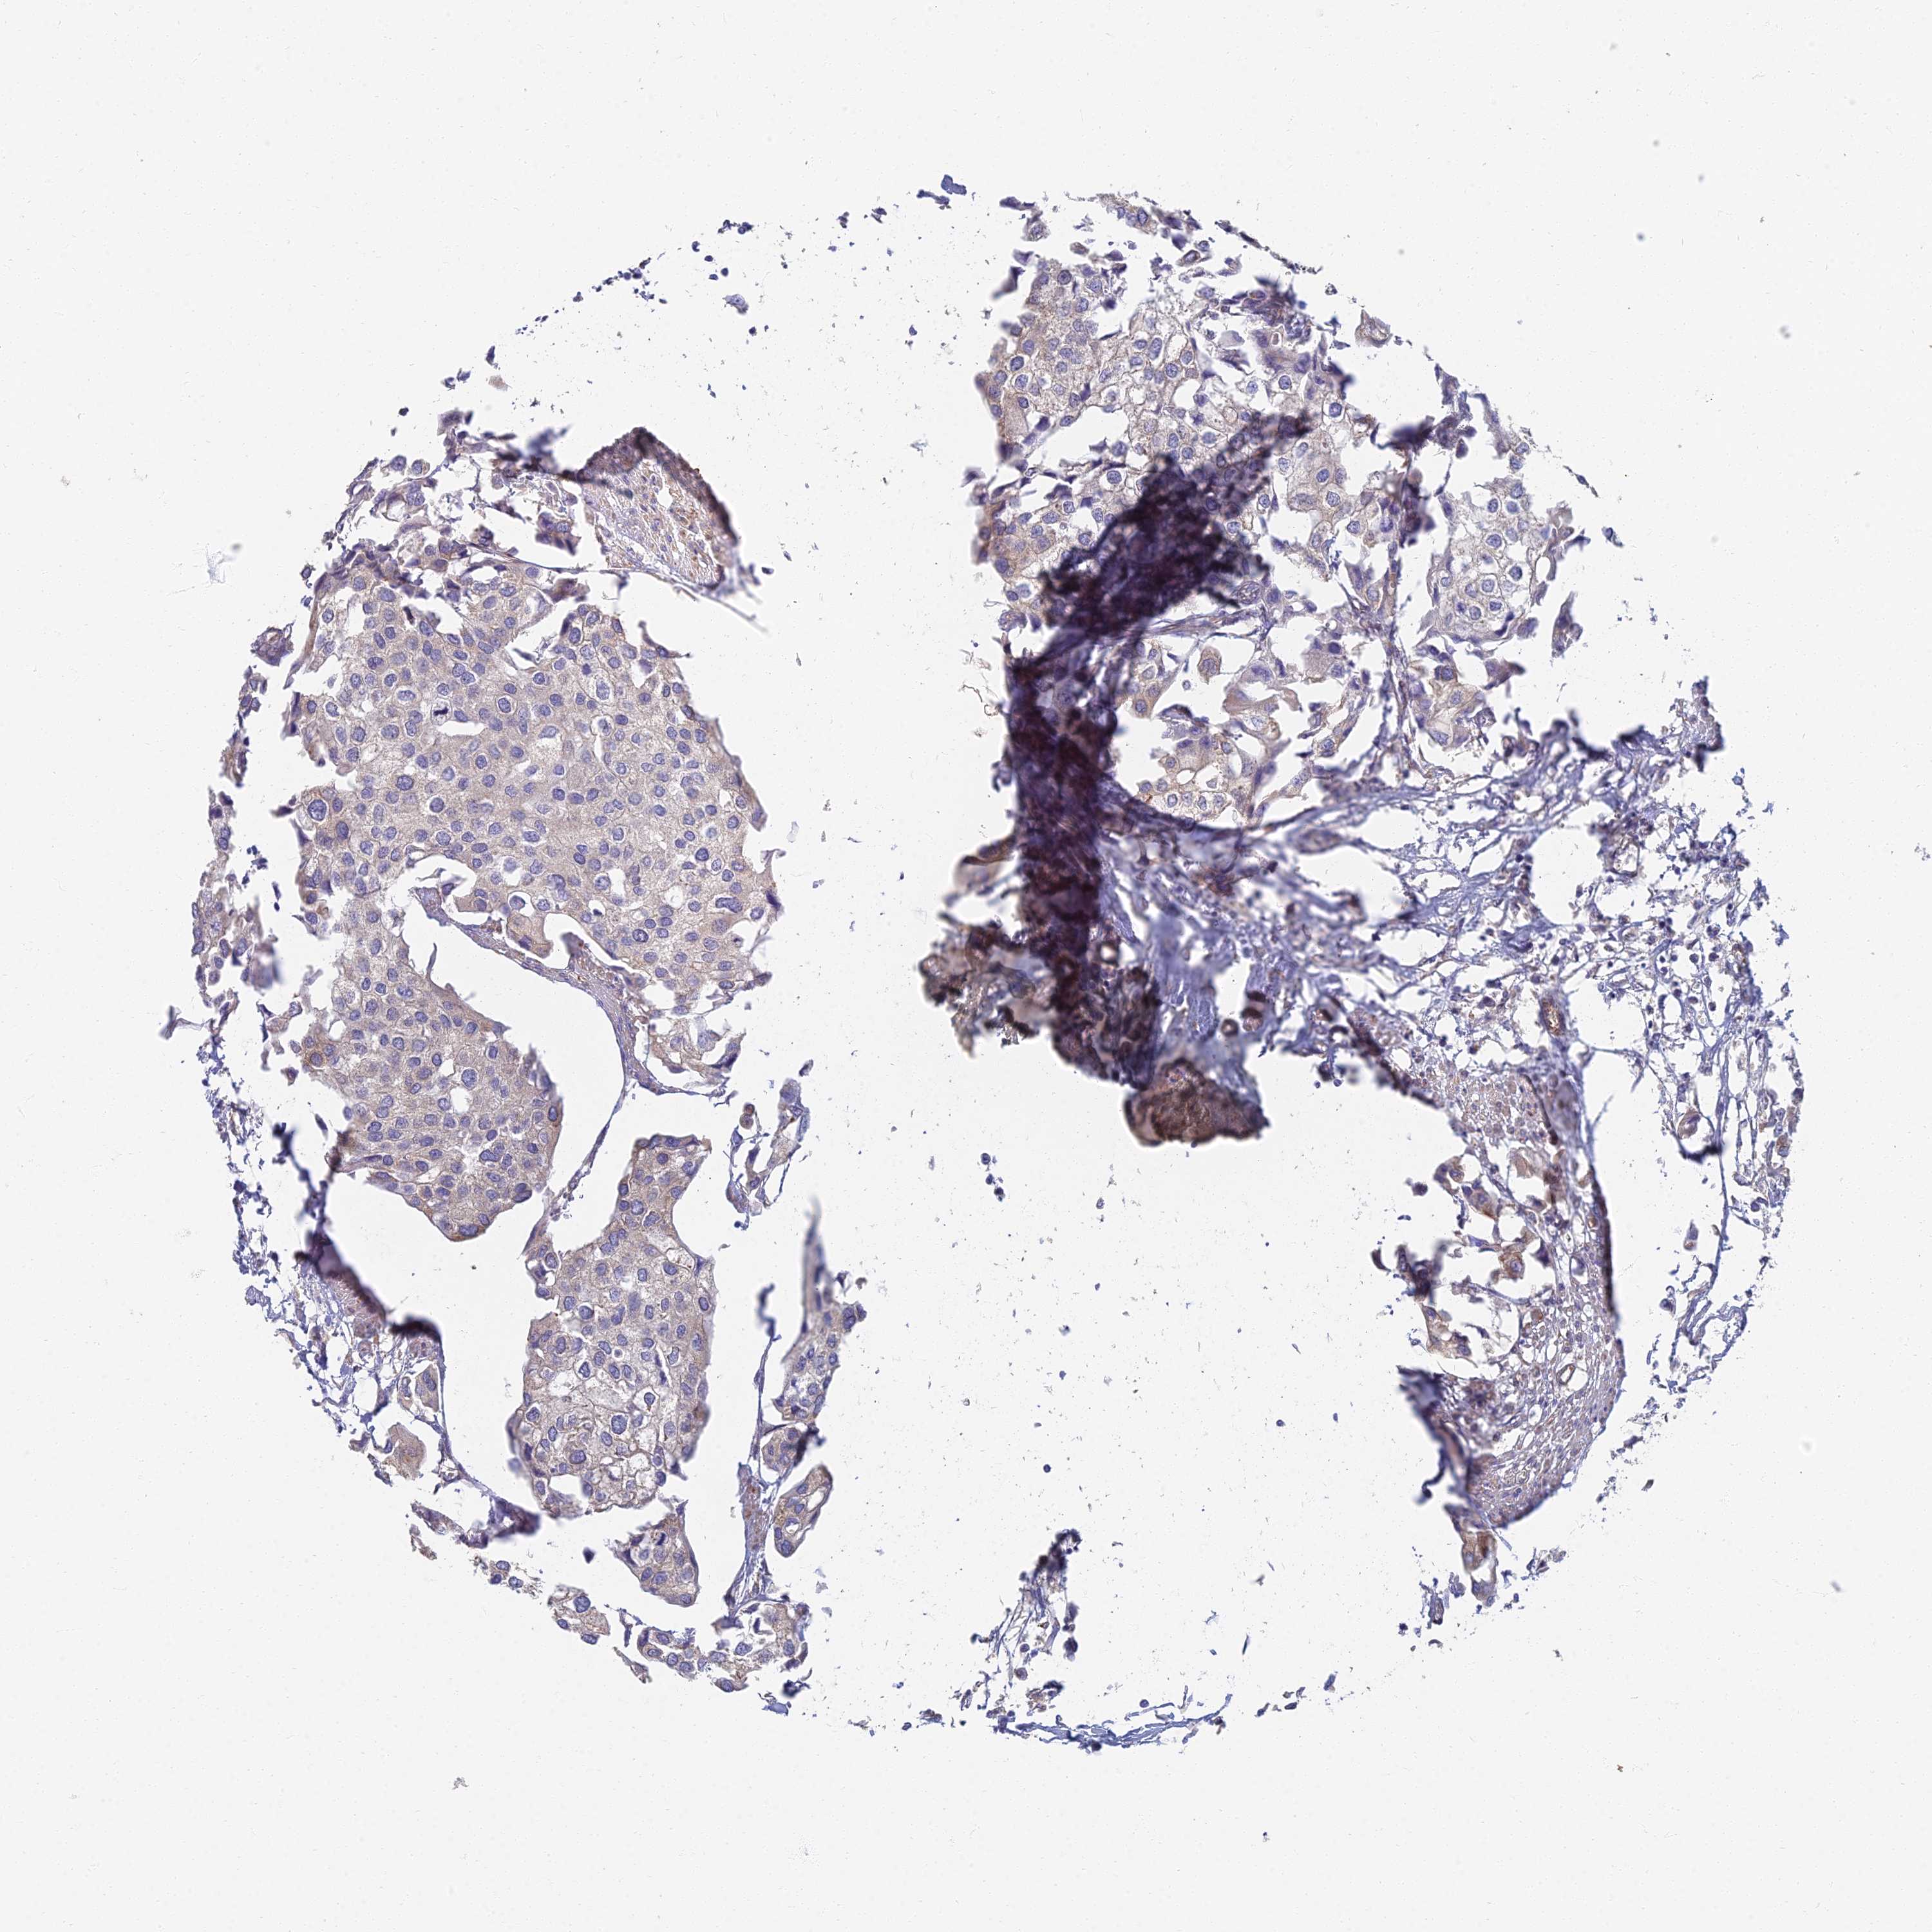

UROTHELIAL CANCER - Protein expressioni

A mouse-over function shows sample information and annotation data. Click on an image to view it in a full screen mode. Samples can be filtered based on level of antibody staining by selecting one or several of the following categories: high, medium, low and not detected. The assay and annotation is described here.

Note that samples used for immunohistochemistry by the Human Protein Atlas do not correspond to samples in the TCGA dataset.

Antibody stainingi

Antibody staining in the annotated cell types in the current human tissue is reported as not detected, low, medium, or high, based on conventional immunohistochemistry profiling in selected tissues. This score is based on the combination of the staining intensity and fraction of stained cells.

Each image is clickable and will lead to virtual microscopy that enables deeper exploration of all samples and also displays staining intensity scores, fraction scores and subcellular localization as well as patient and tissue information for each sample.

Antibody HPA044878

Staining

High

Medium

Low

Not detected

Intensity

Strong

Moderate

Weak

Negative

Quantity

>75%

75%-25%

<25%

None

Location

Nuclear

Cytoplasmic/membranous

Cytoplasmic/membranous,nuclear

Urothelial carcinoma, High grade

Urothelial carcinoma, Low grade